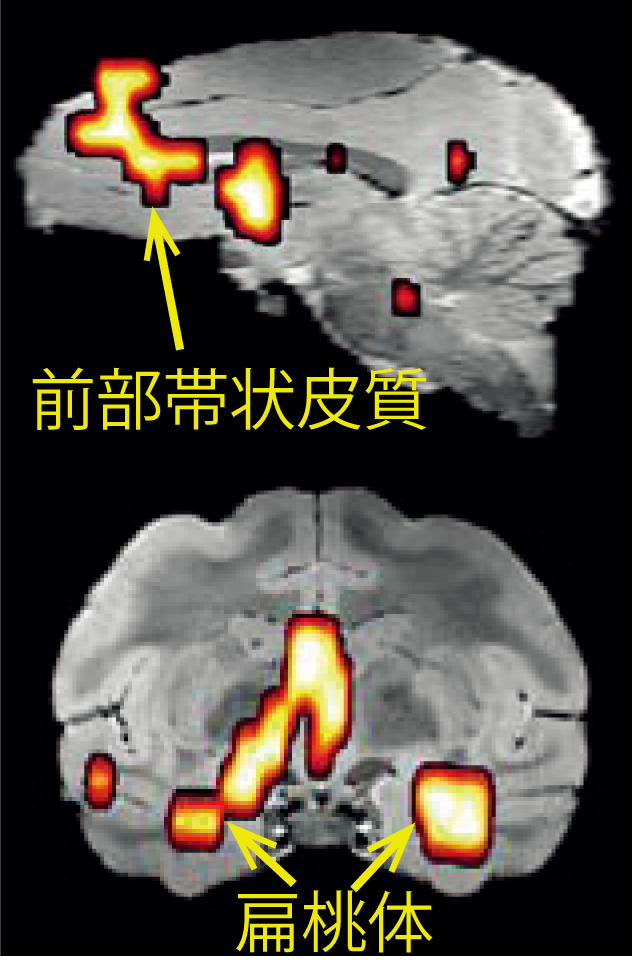

図 運動チックに比べて音声チック中に活動が過剰に亢進したモデルザルの脳部位

前部帯状皮質(上)、扁桃体 (下)で音声チック中に活動の過剰な亢進が見られる。